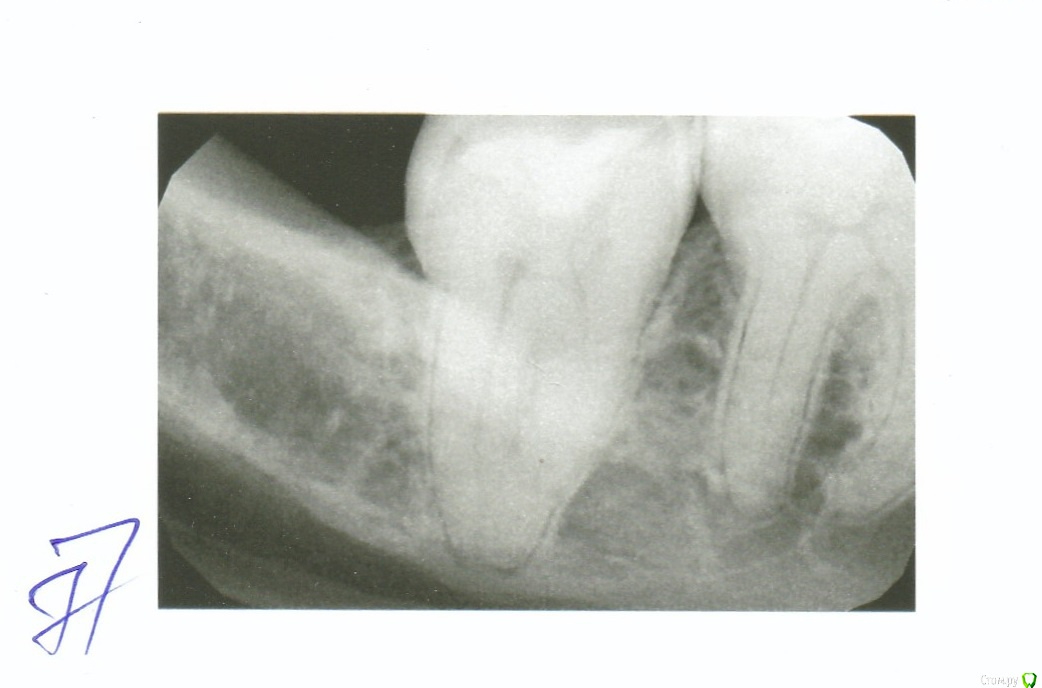

Kraas Опубликовано 25 ноября, 2019 Поделиться Опубликовано 25 ноября, 2019 Добрый день!При удалении зуба мудрости в 47м зубе на снимке было обнаружено воспаление. Зуб мудрости удален, что делать с 47м зубом? Он никогда не болел и сейчас не болит, никак себя не проявляет. Насколько я понимаю что после лечение зуб будет депульпирован с перспективой на протезирование. Хирург когда удалял зуб мудрости предложил удалить 47, я отказался. Теперь вот не знаю что делать с зубом.Спасибо за ответы! Ссылка на комментарий

red_butler Опубликовано 25 ноября, 2019 Поделиться Опубликовано 25 ноября, 2019 не вижу показаний для лечения или удаления, сделайте панорамный Rg 1 Ссылка на комментарий